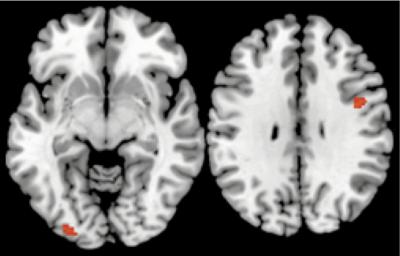

When the participants were initially learning information about the cars and other items, the neuroimaging results showed activation in the visual and prefrontal cortices, regions that are known to be responsible for learning and decision-making. Additionally, during the distractor task, both the visual and prefrontal cortices continued to be active — or reactivated — even though the brain was consciously focused on number memorization.

Third, the results showed that the amount of reactivation within the visual and prefrontal cortices during the distractor task predicted the degree to which participants made better decisions, such as picking the best car in the set.